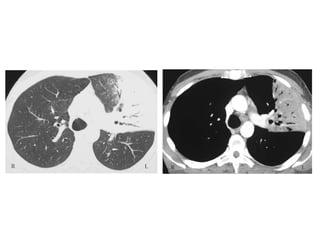

Bat wing edema in a 71-year-old woman with fluid overload and cardiac

failure, chest radiograph (a) and high-resolution CT

scan (b) demonstrate bat wing alveolar edema with a central

distribution and sparing of the lung cortex, the infiltrates resolved

within 32 hours